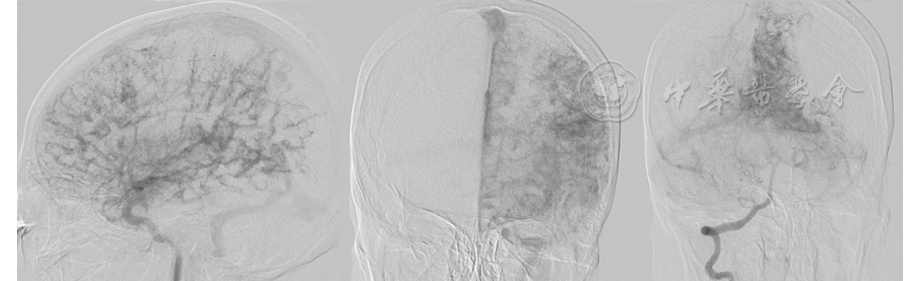

患者女,62岁,因言语不清伴右眼视物不清3 d就诊。血常规、肝肾功能及凝血全套检测均正常。体格检查:血压155/71 mmHg(1 mmHg=0.133 kPa),神清,格拉斯哥昏迷评分(Glasgow coma scale, GCS)15分,定向力正常,口齿不清;双侧瞳孔直径3.0 mm,光反应灵敏,两侧眼球活动无异常,粗测视野右侧同向偏盲;两侧额纹对称,两侧鼻唇沟基本对称,伸舌居中;右下肢可疑5级-,余肢体肌力5级,两侧肌张力无异常,两侧腱反射对称阳性,巴宾斯基征阴性。患者既往无高血压、冠状动脉硬化性心脏病及糖尿病史。头部CT检查示左枕叶低密度,诊断为脑梗死。MRI平扫示左颞叶、枕叶见片状异常信号;T1加权成像(weighted imaging, WI;图1A)呈低信号,局部脑表面见点状、线样高信号,T2液体衰减反转恢复(fluid attenuated inversion recovery, FLAIR)序列成像(图1B)示左颞叶、枕叶斑片状高信号,局部脑表面见点状、线样高信号,即"常春藤"征,并可见粗大流空血管信号,左额叶、颞叶、顶叶及枕叶皮质下轻度信号增高;弥散加权成像(diffusion weighted imaging, DWI;图1C) (b=1 000 s/mm2)示左颞叶、枕叶皮质片状高信号。99Tcm-双半胱乙酯(ethylcysteinate dimer, ECD)SPECT/CT脑血流灌注显像(图1D)示,左额叶、颞叶、顶叶及枕叶大范围脑血流灌注减低区,局部脑血流(regional cerebral blood flow, rCBF)为26.75~37.91 ml·100 g-1·min-1,右小脑半球局部脑血流灌注减低,提示交叉性小脑失联络。数字减影血管造影(digital subtraction angiography, DSA;图2)示左侧大脑半球弥漫性异常血管增生,病灶弥漫性分布,供血动脉累及左大脑前动脉、左大脑中动脉及左大脑后动脉,左颈外动脉造影额颞部可见多处硬膜血管向颅内代偿。最终诊断:增殖性脑血管病(cerebral proliferative angiopathy, CPA),左颞叶、枕叶脑梗死。予营养神经、改善微循环等保守治疗后,患者症状好转并出院。

CPA的诊断主要依赖于DSA,其表现为累及整个脑叶甚至整个大脑半球的弥漫性增生的血管网,呈"泥浆样"改变,无优势供血动脉及引流静脉或与血流相关的动脉瘤,病灶边界不清,存在混合的正常脑实质[1]。99Tcm-ECD SPECT/CT脑血流灌注显像可计算出不同部位的rCBF,而同机CT能弥补SPECT图像组织分辨率低、解剖结构不清晰的不足,从而提高对缺血性脑血管病的诊断能效[4]。本例SPECT/CT脑血流灌注显像显示,患者左大脑半球弥漫rCBF减低,范围明显大于常规MRI异常信号区,与文献[5]报道一致,且负荷脑血流灌注显像提示脑血流储备功能降低,CPA受累区域为低灌注状态,血流动力学特点更接近烟雾病[5,6]。因此,对于疑似脑卒中的患者,当SPECT/CT脑血流灌注显像所示缺血范围明显大于CT和(或)MRI所示时,或显像呈现整个大脑半球、多个脑叶大范围的明显脑缺血改变时,需考虑CPA的可能,建议进一步行DSA检查明确诊断。本例SPECT/CT脑血流灌注显像还观察到交叉性小脑失联络现象,而CT及MRI均未显示,也体现了脑血流灌注功能显像的优势。